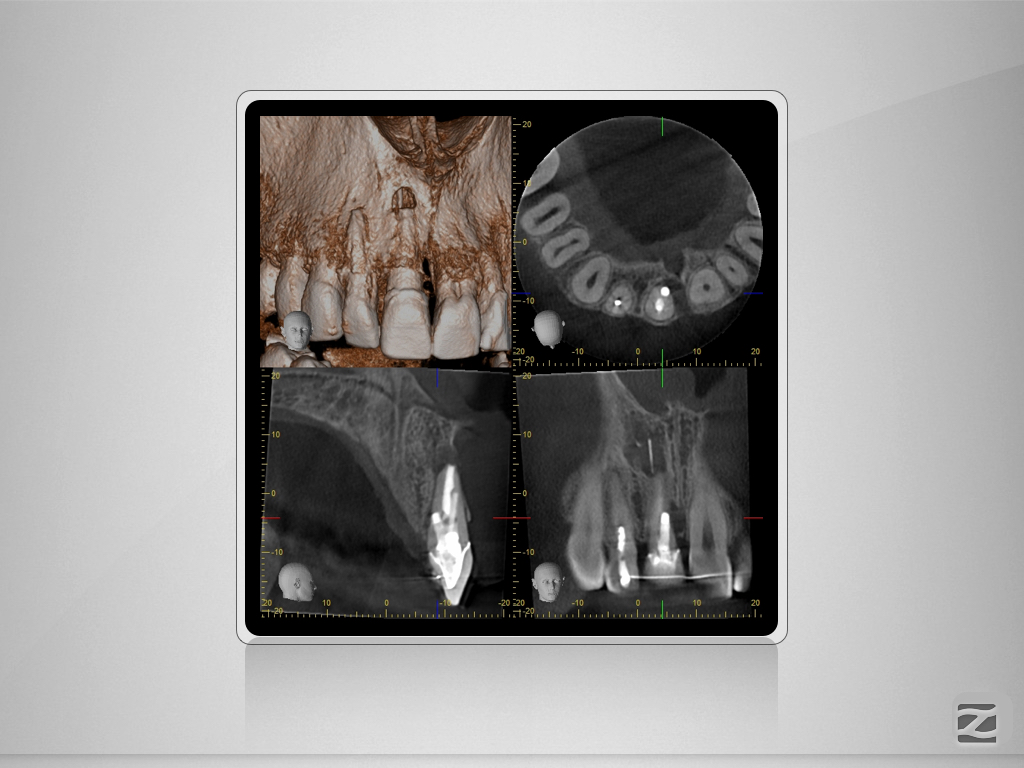

11D.004 Veröffentlicht 26. Oktober 2015 am 1024 × 768 in Saving hopeless Teeth – DVT gestützte Behandlungsplanung